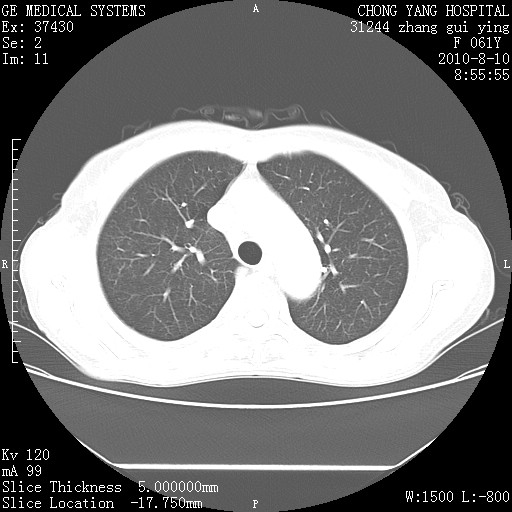

标题: CT28314:F61Y胸部增强,发热咳嗽一周入院,后面的为一周前平

1、支持考虑右侧中央型肺癌伴右肺中叶节段性不张及下叶支气管黏液痰栓    2、左肺上叶舌段感染。

我也觉得右肺中叶支气管受累

确切的说:1:右肺下叶中心型肺癌侵及中叶支气管并中叶不张,纵膈淋巴结转移。2:左肺舌叶炎症。3:右侧胸腔少量积液

块影平扫32hu,动静脉期62-70hu.

右肺下叶内基底段近膈不规则肿块,考虑右肺下叶周围型肺癌可能性大。